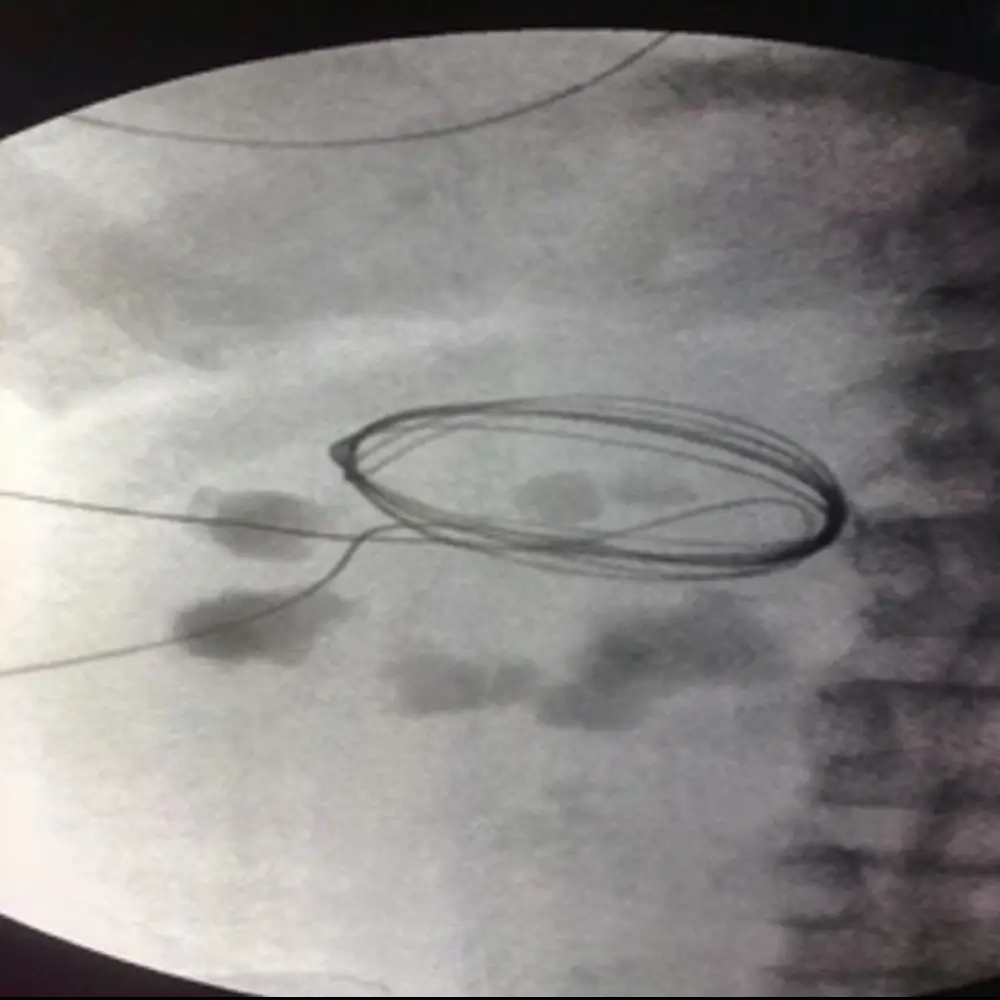

Clinic Procedures Gallery

A visual showcase of advanced urological procedures, highlighting our expertise, technology, and commitment to patient care.